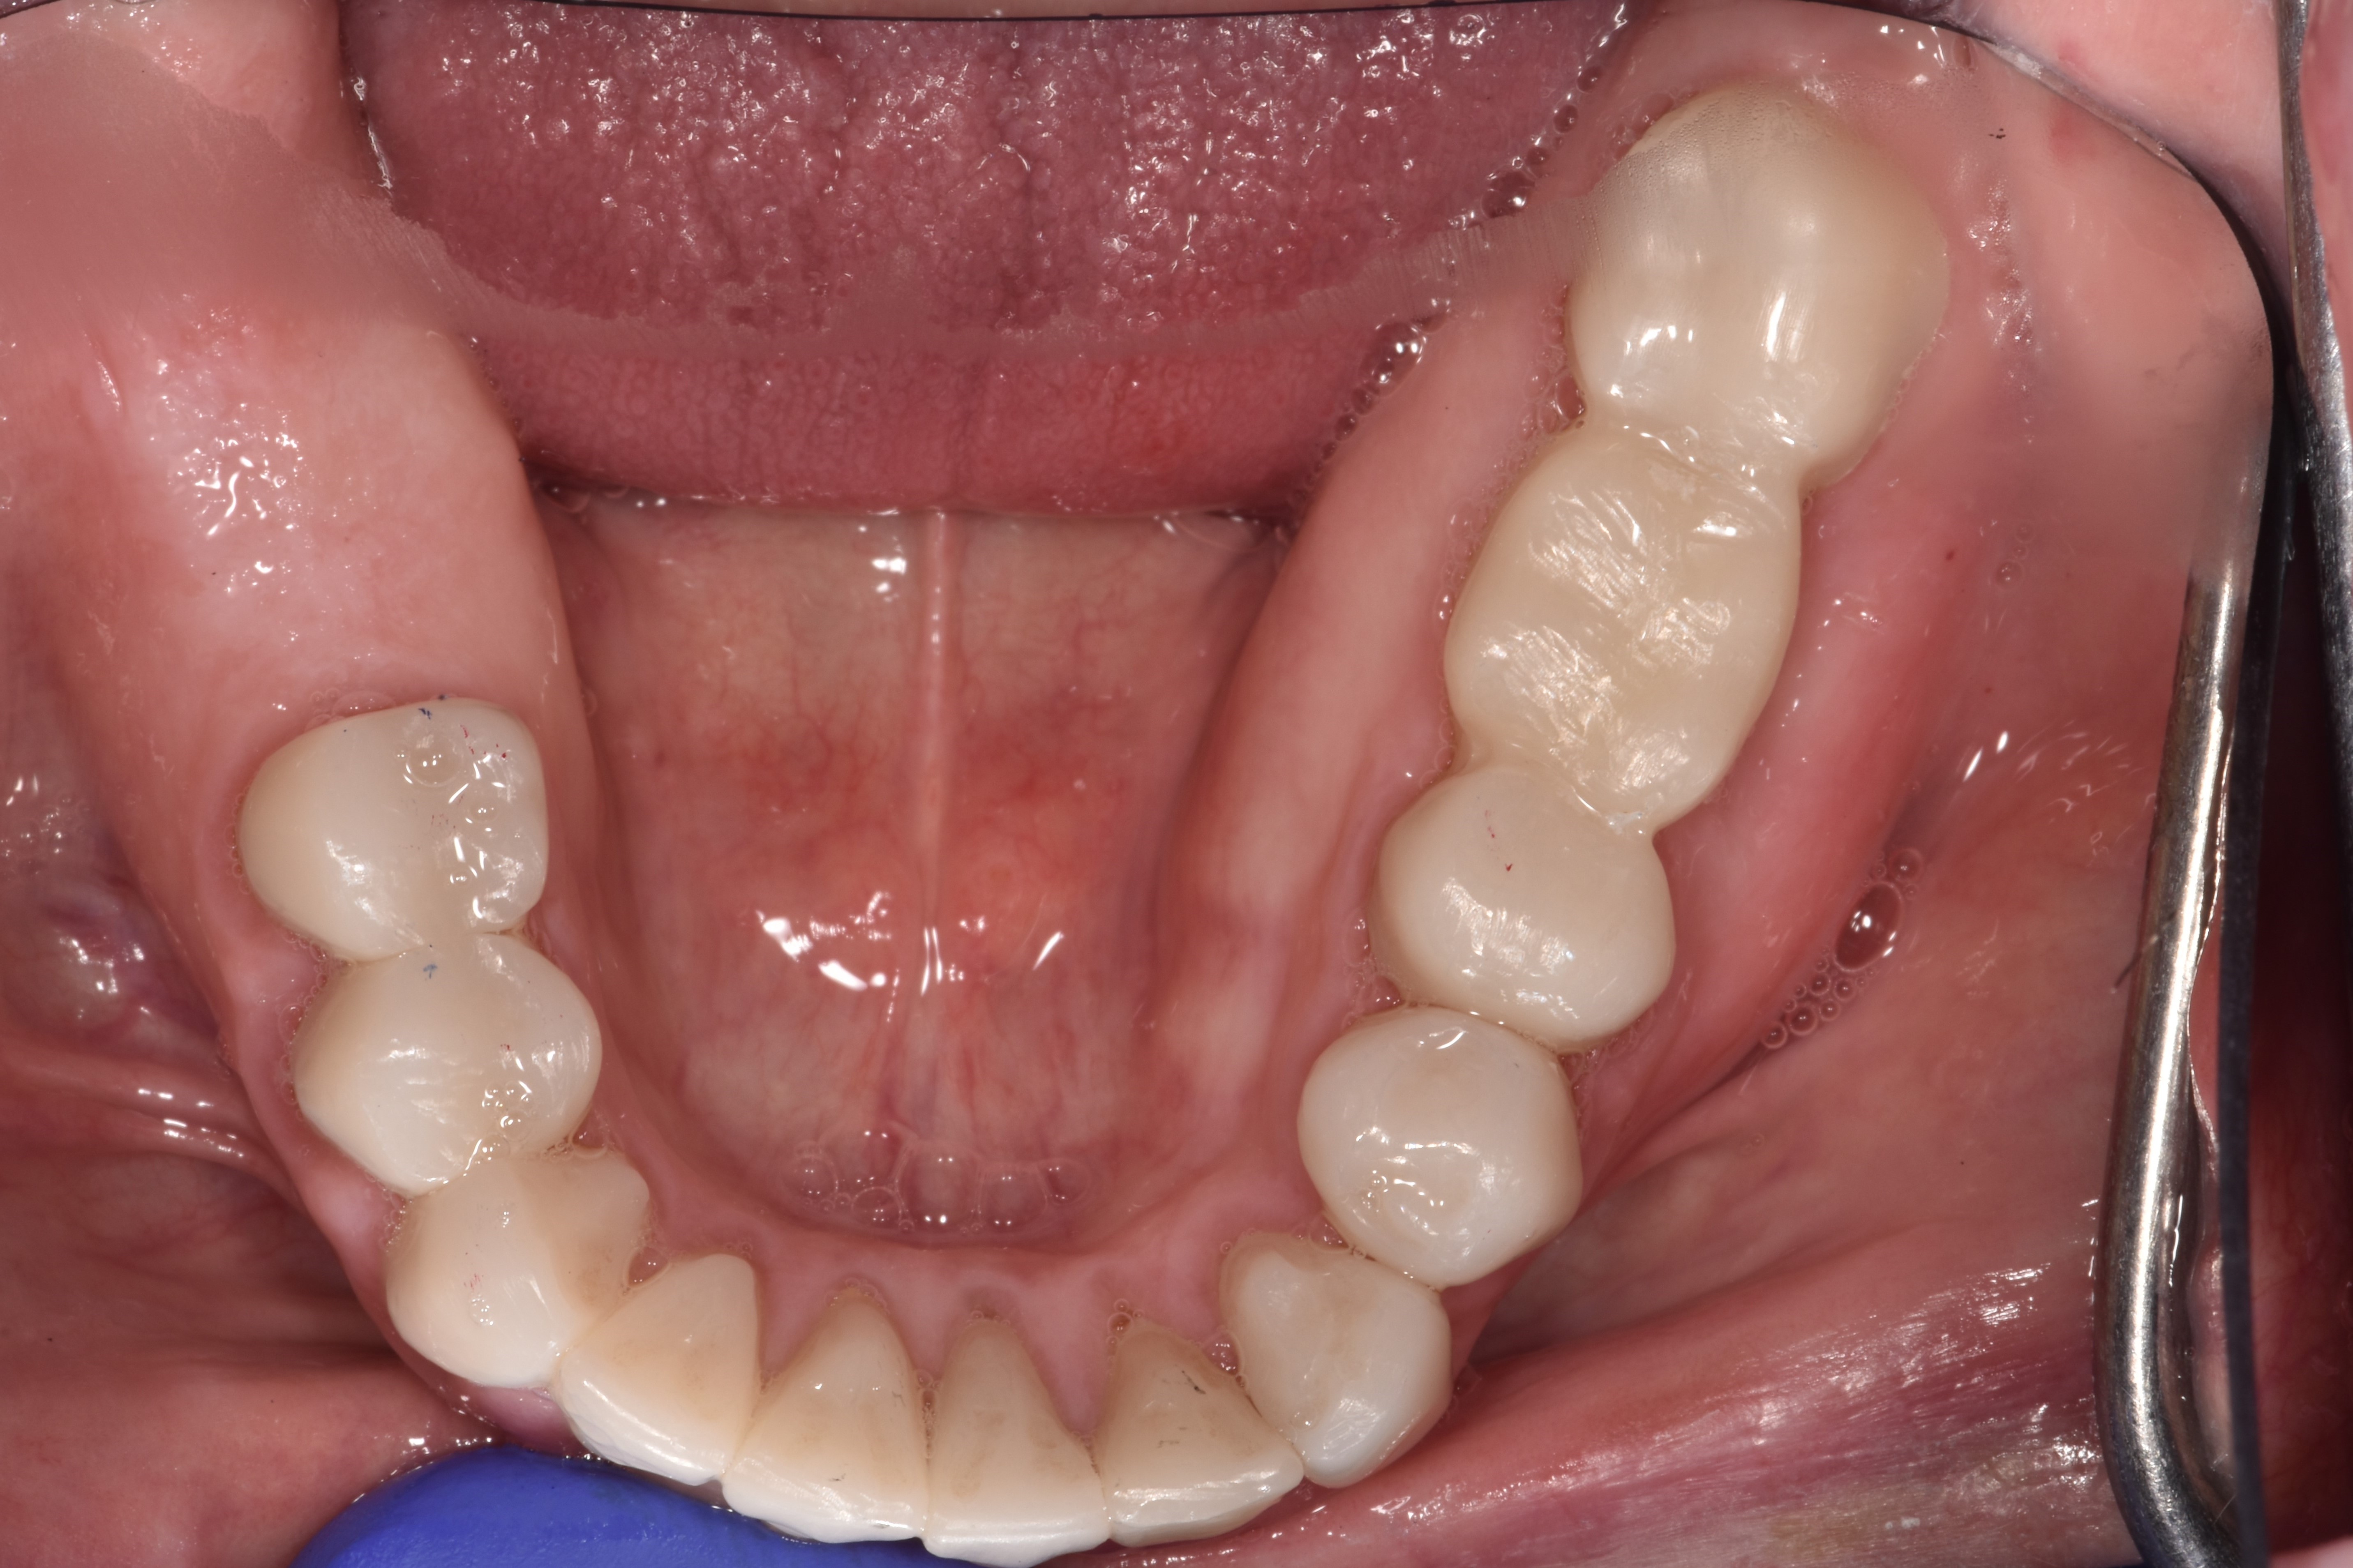

After clinical evaluation and treatment planning, it was determined that the state of the patient's dentition was not hopeless and that her teeth could be restored. The patient decided that she would like to try to preserve her natural teeth with a full-mouth crown and bridge rehabilitation, and to have any salvageable teeth treated with root canal therapy instead of extraction, if possible. After a thorough examination, it was determined that one tooth would need to be extracted (tooth

No. 19) and one would need root canal therapy (tooth No. 6). Twenty-four units of crown and bridge were needed. In order to save the patient the cost of sending her crowns out to a laboratory for fabrication, it was agreed that the restorations would be made in-house. A fully digital workflow was implemented for all planning and restorative work, where possible.

After a dental prophylaxis cleaning, the patient's mouth was scanned with an intraoral scanner for preoperative models (Figure 6).  An upper and lower dentate scan was obtained with corresponding bite records. The bite was recorded at maximum intercuspation. Tooth length measurements were made, and it was found that the maxillary central incisors were only 8 mm in length, owing to prolonged bruxism and incisal wear.

Fig. 4